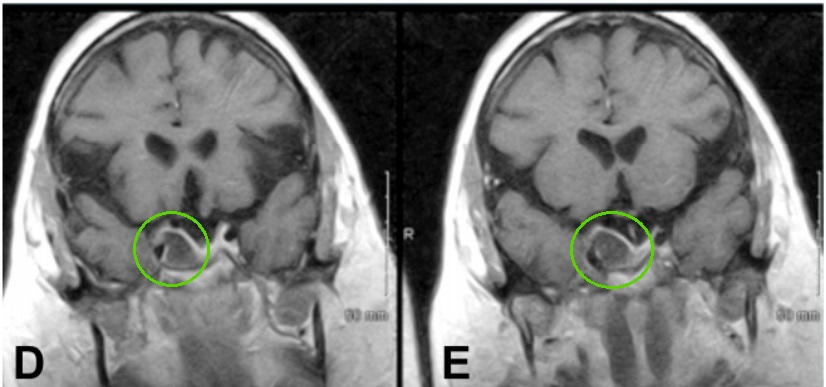

▼术后MR患者动眼神经麻痹消退,影像学检查术后3年无复发。

术后磁共振成像证实了肿瘤达到了肉眼全切。

术后,患者的动眼神经麻痹得到缓解,手术恢复过程顺利,她继续服用与术前相同的药物。病理学鉴定确认肿瘤为垂体腺瘤,未发现恶性证据。三年后的随访影像学检查显示未见肿瘤复发。